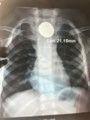

▲胸片 错误的治疗 异物卡食管却当胃病医 据浩浩妈回忆,儿子误吞纽扣电池极有可能发生在7月17号。“当时我没发现,他可能是吞的玩具里的纽扣电池。”那天中午,浩浩吃不下饭,把食物吞了又吐,浩浩妈以为是儿子的胃出了问题,于是一直当成胃病治疗。 错误的判断导致病情持续恶化,直到8月14日,看着依然只能吃流食、病情不断加重的儿子,浩浩妈带着他去新都当地一家医院做检查——胸片显示,一个直径2.2厘米的圆形异物卡在了浩浩食管的中上部。“中上部的大血管比较丰富,危险性更大,医生说病情很紧急,告诉我小医院做不了,建议到市级医院看看。”